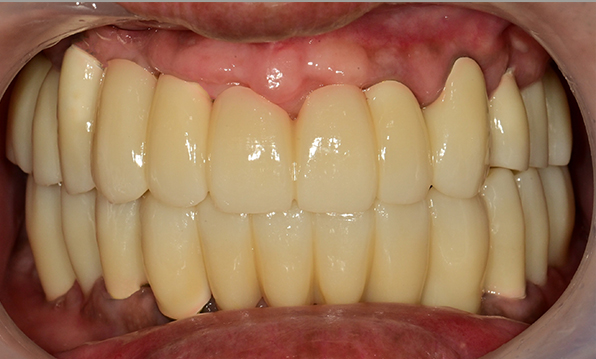

치아가 하나도 남아있지 않거나 전체적으로 상실된 경우 추천합니다.

전체 임플란트가 필요한 경우

치아가 얼마 남아있지 않은 경우

치주질환이 심해, 치아가 있더라도 제 기능을 하지 못하는 경우

틀니 사용이 불편한 경우